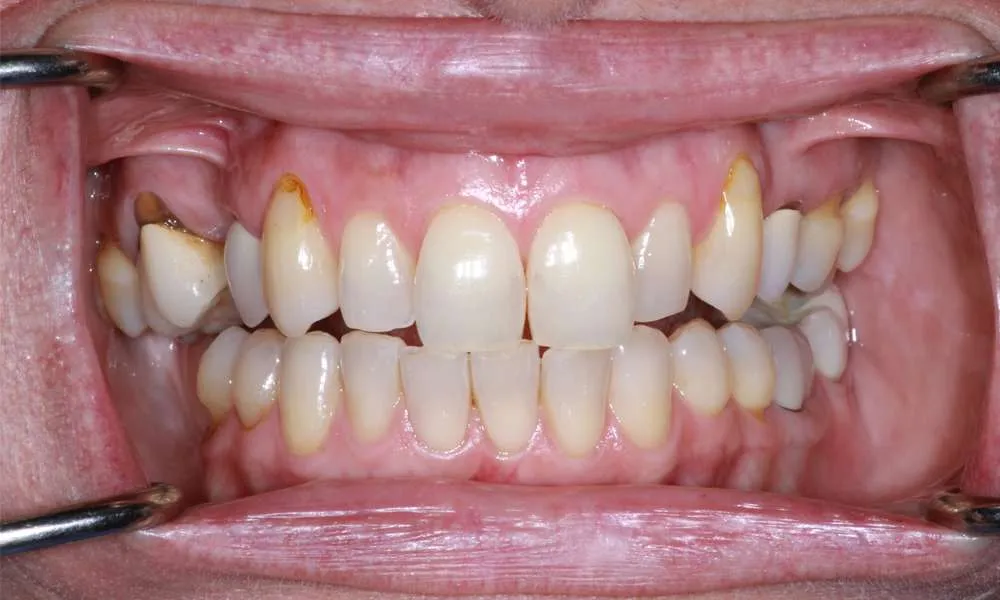

Real Stories, Real Results: Case Studies Showcasing How Our Personalized Approach Transforms Smiles and Lives

Witness the Remarkable Changes We Can Achieve